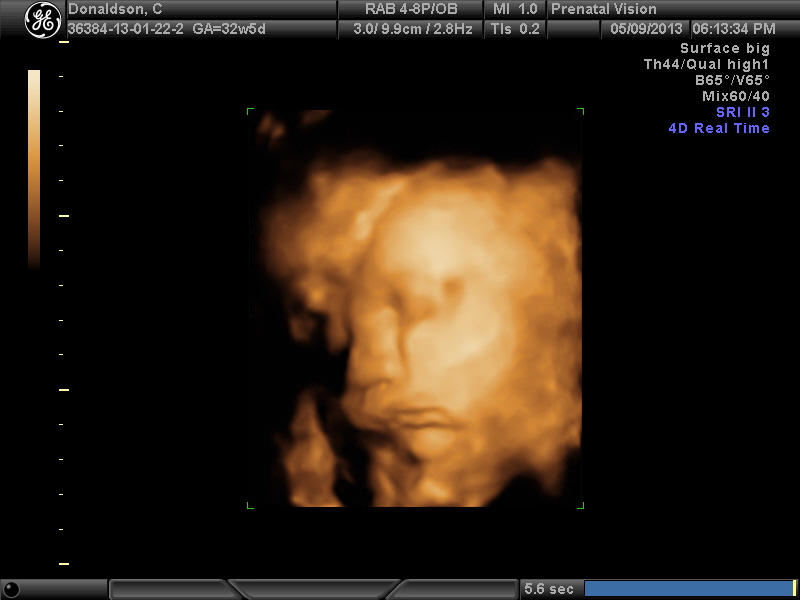

IMAGES_10 May 13, 2013 by Courtney Leave a comment ← Previous Image Next Image → 32w5d Like Loading...